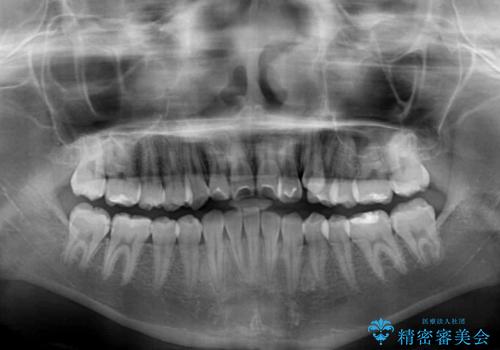

奥歯の咬み合わせは左右とも理想的なものでしたが、下顎前歯が1本欠損しているため、上下のバランスを保つことが難しい歯列でした。

唇を閉じたときに上顎前歯が下顎の唇に乗っかる印象があったため、八重歯の後方にある小臼歯を1本抜歯することとしました。